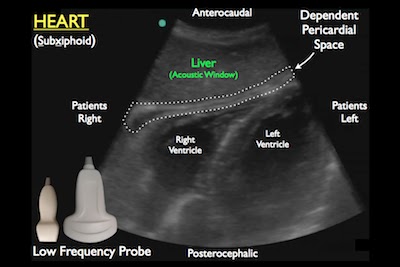

- Component: Heart (Subxiphoid)

- Probe: Phased array probe (3.5 – 5 MHz)

- Location: Subxiphoid, point toward left scapula